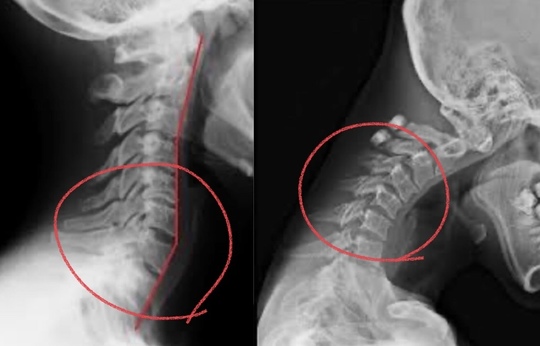

上位頸椎と上位胸椎が固まりやすくなりやすい場所になり、過剰に動いてしまう下位頸椎にヘルニアが多くなります。

過〇は過剰に動くため痛みが出やすい場所になる

〇の部分が過剰に動く部分で、その上下の部分はあまり動かない場所になります。

首も腰も下側にヘルニアが多くなる構造になっております。

赤い□は凝り固まりやすい場所